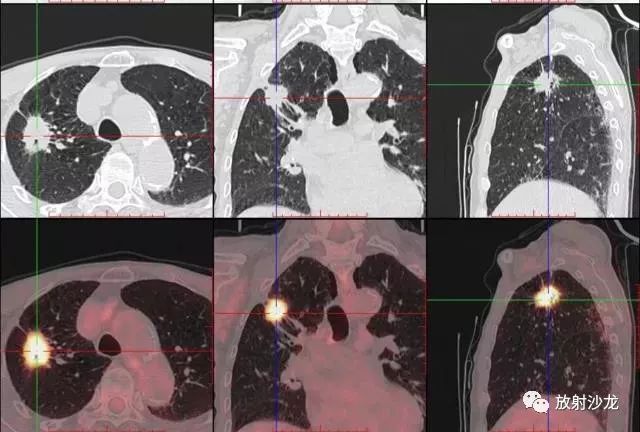

PET-CT是目前世界上最先進的核醫(yī)學(xué)分子影像設(shè)備,中文稱為正電子發(fā)射計算機斷層/X 線計算機體層成像。

PET-CT等于PET+CT,包含PET(功能分子影像)與CT(解剖影像)的最優(yōu)化組合;即同時具有PET和CT的功能,但它絕不是二者功能的簡單疊加,因為PET與CT優(yōu)勢互補,“1+1>2”。PET-CT除了具備PET和CT各自的功能外,其獨有的融合圖像,將PET圖像與CT圖像融合, 可以同時反映病灶的代謝,可以早期診斷疾病的同時,明顯提高診斷的準確性。